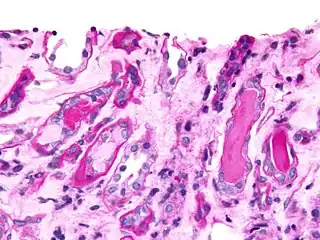

Histopathology

A bone marrow biopsy is usually performed to estimate the percentage of bone marrow occupied by plasma cells. This percentage is used in the diagnostic criteria for myeloma. Immunohistochemistry (staining particular cell types using antibodies against surface proteins) can detect plasma cells that express immunoglobulin in the cytoplasm and occasionally on the cell surface; myeloma cells are often CD56, CD38, CD138, and CD319 positive and CD19, CD20, and CD45 negative.[14] Flow cytometry is often used to establish the clonal nature of the plasma cells, which will generally express only kappa or lambda light chain. Cytogenetics may also be performed in myeloma for prognostic purposes, including a myeloma-specific fluorescent in situ hybridization and virtual karyotype.

The plasma cells seen in multiple myeloma have several possible morphologies. First, they could have the appearance of a normal plasma cell, a large cell two or three times the size of a peripheral lymphocyte. Because they are actively producing antibodies, the Golgi apparatus typically produces a light-colored area adjacent to the nucleus, called a perinuclear halo. The single nucleus (with inside a single nucleolus with vesicular nuclear chromatin) is eccentric, displaced by an abundant cytoplasm. Other common morphologies seen, but which are not usual in normal plasma cells, include:

- Bizarre cells, which are multinucleated

- Mott cells, containing multiple clustered cytoplasmic droplets or other inclusions (sometimes confused with auer rods, commonly seen in myeloid blasts)

- Flame cells, having a fiery red cytoplasm[42][43]